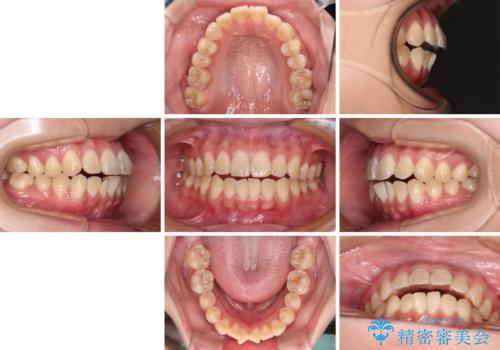

舌の突出癖による開咬と前歯の突出 インビザライン矯正治療

- 上下前歯の非接触と叢生を気にして来院された患者様です。

開咬の改善はインビザラインの最も得意とするところであるため、インビザラインを用いて矯正治療を行うこととしました。

途中海外転勤の可能性が高いとのこともあり、ワイヤー装置ではなくインビザライン矯正が最適な治療ツールとなりました。

治療開始直後に上顎前歯に激しい痛みが発現し、矯正治療を休んだり、マウスピースの装着時間を短くしたりと工夫をしましたが、残念ながら治療途中で失活していることが分かりました。

矯正治療の途中で前歯の根管治療とオールセラミッククラウンによる補綴治療を行い、その後インビザライン1セットを用いて細かい部分を仕上げました。